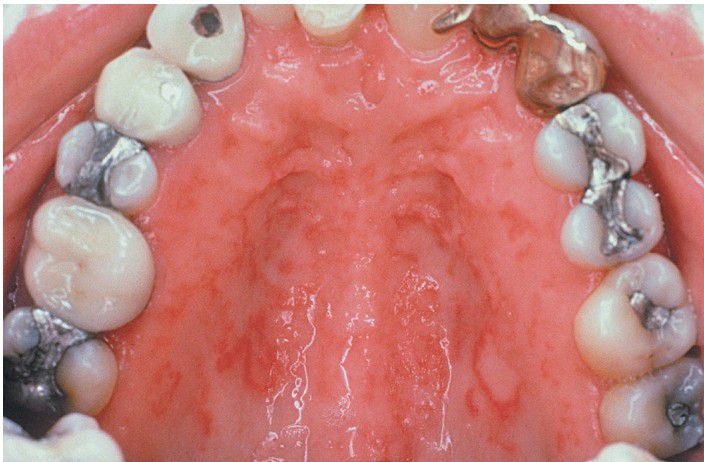

This is an example of relatively rare involvement of the oral mucosa by psoriasis. The erythematous linear patches tended to flare with the patient’s cutaneous lesions. (Courtesy of Dr. George Blozis.)